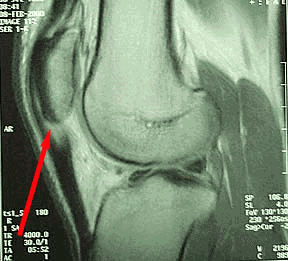

La resonancia magnética (RM) y la ecografía son muy sensibles para detectar alteraciones tendinosas tanto en pacientes con síntomas como en asintomáticos. Esto genera un alto número de falsos positivos, lo que limita su utilidad en pruebas de rutina.

Resonancia magnética de rodilla